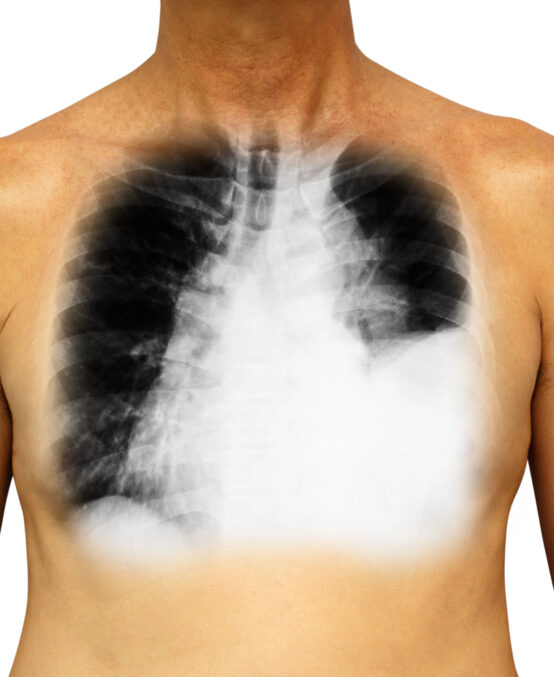

Ultrasound-guided thoracentesis is used to drain excess fluid from the pleural space (the area between the lung and chest wall).

Ultrasound imaging  is to precisely locate the fluid collection within the pleural space. After local anesthetic is provided,  a small needle or thin plastic tube (catheter) is inserted through the skin into the pleural space. The excess fluid is aspirated (withdrawn) using a catheter. Average duration for drainage is 5 minutes. Upon completion of the drainage, a chest x-ray is performed. Recovery is usually straightforward, with most patients experiencing minimal cough symptoms.